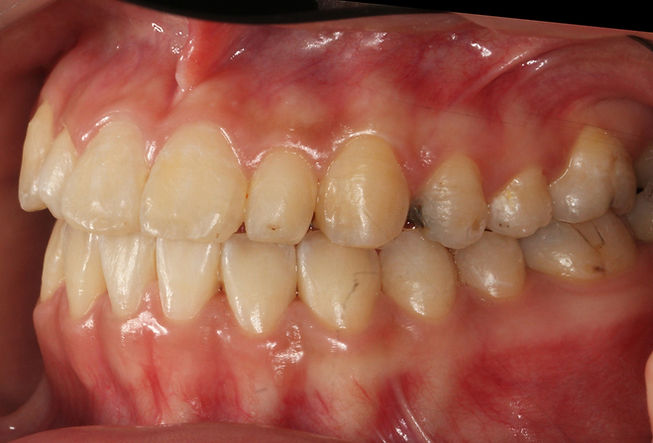

Before : 반대교합을 보이는 성인 주걱턱 케이스

After : 반대교합 개선

​심한 반대교합을 보이는 성인 주걱턱 환자분 입니다.

상악 악궁확장과 함께 하악 치아의 미니스크류를 이용한 후방이동

그리고 적절한 턱관절의 재위치를 이용해 반대교합을 개선하였습니다.